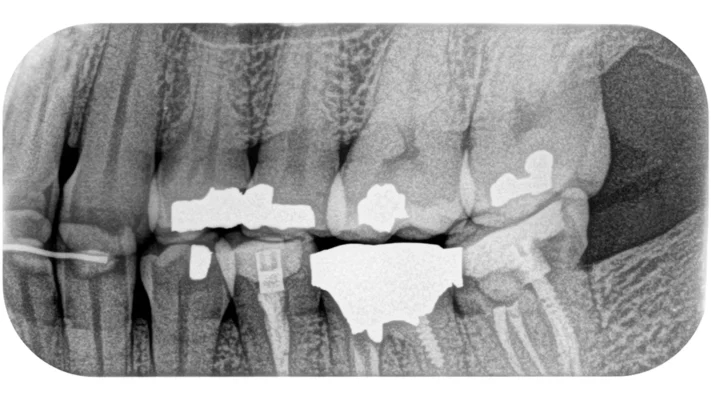

Na rozdíl od ostatních zobrazovacích systémů na záznamové fólie, není systém CS 7600 zablokován v průběhu skenování fólie. Technologií Scan and Go je každá záznamová fólie před vyšetřením elektronicky identifikována a snímky jsou automaticky odeslány do příslušného počítače a složky konkrétního vyšetřovaného pacienta. Tím se nejen odstraňuje čas čekání v průběhu skenování fólie, ale také riziko chyb při identifikaci snímků.

Práce se záznamovými fóliemi je stejně jednoduchá jako s filmem. CS 7600 tedy zachovává pracovní návyky, ale je rychlejší a výkonnější než tradiční snímkování na film. Rutinní vyšetření jsou automatizována a na zabudovaném monitoru lze ihned sledovat úspěšnost vyšetření bez nutnosti odbíhat k počítači.

• Zobrazovací software s intuitivní navigací získá ze snímků maximum diagnostické informace